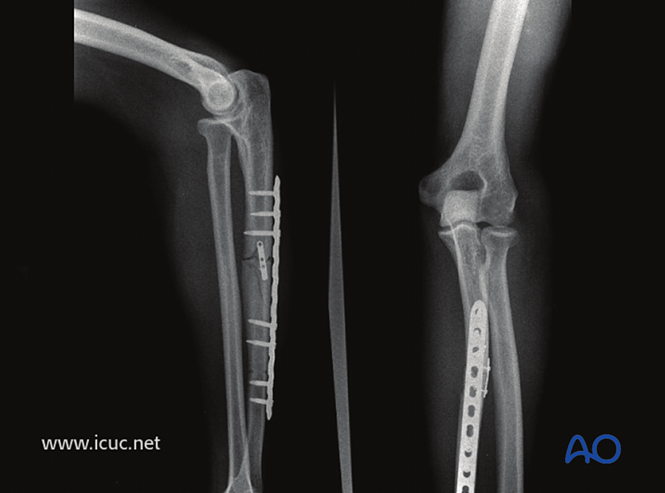

正位片显示肱桡关节复位良好。

采用桥接固定联合复位钢板治疗该复杂孟氏骨折。

4周时骨折仍可见,但肘关节复位良好。

49周时的正位和侧位影像。

X线检查●应按照当地诊疗规范进行随访X线检查。建议在2周时进行X线检查,确保桡骨头位置保持良好,之后在6周、12周和1年时检查,评估尺骨愈合情况。●若X线显示尺骨愈合进展满意,约术后8周可开始负重。●该病例展示了孟氏骨折术前和术后的X线影像。

术前

术后

1年后